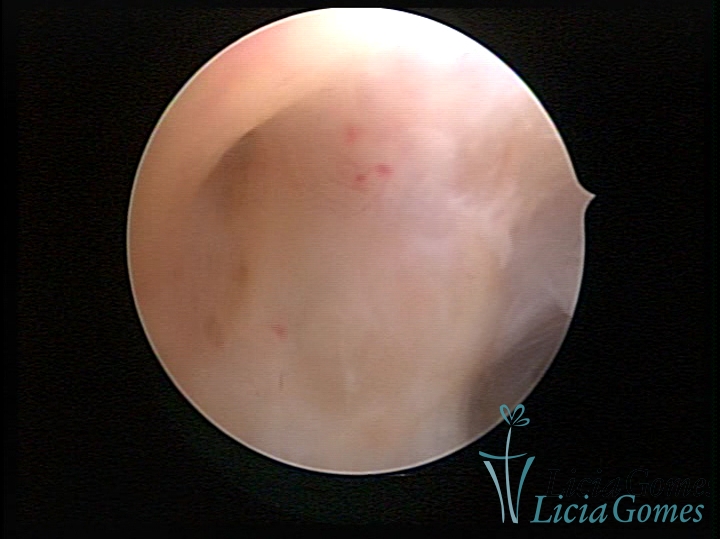

FIBROUS SYNECHIA

Uterine synechiae are scars (adherence) between the surface of the uterine walls, which may occur after the surgical procedure, uterine curettage, or after an inflammatory process in the uterine cavity (endometritis), which may lead to menstrual changes, infertility and obstetric complication such as abortion and premature birth.